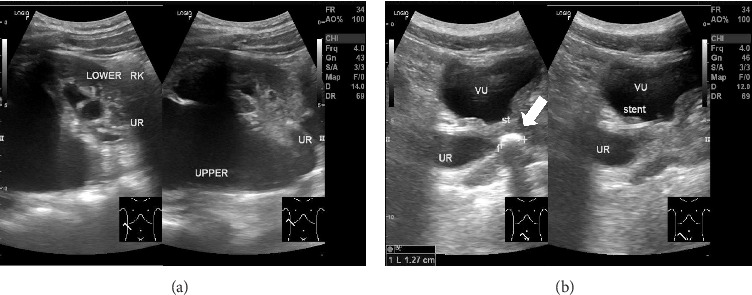

双肾,虽然相对罕见(发生在1%-4%的病例中),但当与尿路症状相关时,可构成重大的临床挑战。需要干预的并发症包括结石形成、尿路梗阻和反流疾病。我们报告一例22岁男性右肾完全双侧伴输尿管远端结石引起的上段肾积水,经超声诊断并术中逆行肾盂造影(RPG)证实。最终通过输尿管镜(URS)碎石术治疗。

Duplex kidneys, though relatively uncommon (occurring in 1%-4% of the cases), can pose significant clinical challenges when associated with urinary tract symptoms. Complications requiring intervention include stone formation, urinary obstruction, and reflux disease. We present the case of a 22-year-old male with complete duplex right kidney with upper moiety hydronephrosis due to a distal ureteral stone, diagnosed by ultrasonography and confirmed with intraoperative retrograde pyelography (RPG). Definitive management was achieved via ureteroscopy (URS) lithotripsy.